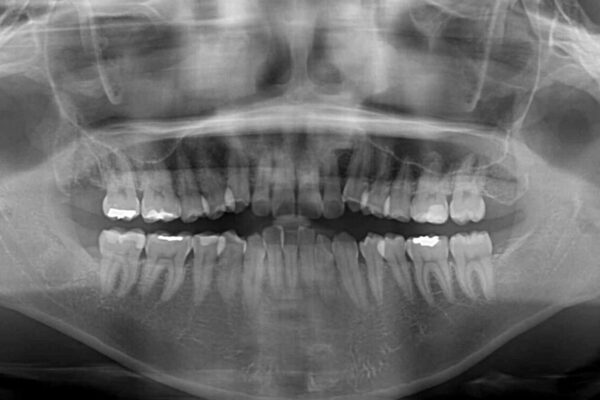

前歯の叢生と八重歯を気にして来院された患者様です。

治療計画

目立たない装置を希望とのことで、インビザラインにて矯正治療を行うこととしました。

インビザライン単体で改善することも可能ですが、八重歯とその後方にある歯列を確実移動させないと、上下正中がずれてしまう可能性があります。

インビザライン単体での治療ではなく、カリエール・ディスタライザーという補助装置を併用して、より確実性を上げることとしました。

補助装置で八重歯を解消しながら、並行してインビザラインで歯列を整えることとしました。